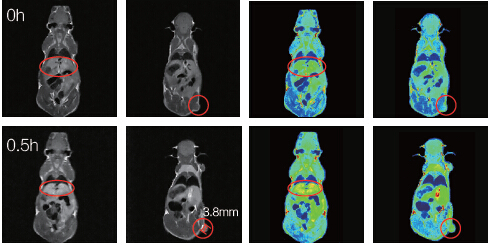

小鼠腫瘤直徑3.8mm;打入新型Mn螯合造影劑0.5h之后,通過灰度平均值計算,發(fā)現(xiàn)肝臟與腫瘤造影明顯。